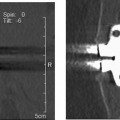

46 The Total Facet Arthroplasty System (TFAS) (Archus Orthopedics, Inc., Redmond, WA) is designed as a total joint replacement of the facets, employing proven technologies and approaches used successfully in total hip and total knee arthroplasty. It is a pedicle-based system that replaces the articulating zygapophyseal joint. The TFAS (Fig. 46–1) was invented by Mark Reiley, M.D., and designed in conjunction with Archus Orthopedics, Inc., as a patented, articulating joint prosthesis intended to provide stabilization of spinal segments in skeletally mature patients as an adjunct to laminectomy, laminotomy, neural decompression, and facetectomy in the treatment of several acute or chronic instabilities or deformities of the lumbar spine, including degenerative disease of the facets, degenerative disease of the facets with instability, grade I degenerative spondylolisthesis with objective evidence of neurological impairment, or central or lateral spinal stenosis. Although stability in all of these cases can be restored surgically with a properly designed implant, as in the case of pedicle rod fusion technologies, to provide a better outcome to the patient in terms of functionality and reduced incidence of complications, a “motion restoring” device that dynamically stabilizes and restores normal motions to the spine (TFAS) has been designed. With the advent of motion-preserving technology in the treatment of spinal disorders, many new products are positioning themselves as treatment alternatives to instrumented fusion. Many of these concepts are incremental line extensions of current fusion applications, as compared with TFAS, which represents a significant advancement in the treatment of posterior lumbar pathologies. Today, these pathologies are most frequently addressed via wide decompression procedures, which often lead to instability at the affected levels. Currently, instrumented fusion hardware is most commonly applied to address these iatrogenic instabilities. Adjacent level disease will be impacted at some level by motion-preserving technologies such as TFAS. The goal of these motion-preservation devices should be to re-create segmental function while attempting to restore stability and physiological motion to improve the biomechanics of the patient’s spine over the short and long term. With the advent of motion preservation devices for spine arthroplasty such as total disk and nucleus prosthetic replacements, the role of the facet joints in the etiology of spinal pathology, as well as the effect of surgical intervention on its temporal changes in physiology, contribution to biomechanics, and effect on the natural trajectory of spine disease, has been newly scrutinized.1–3 In the context of the functional spinal unit (FSU) segment biomechanics, the intervertebral disk, facets, and ligaments all play a key role. In general these structures have three main roles: to stabilize the vertebrae relative to each other and protect the nerves through a range of motion and loads; to provide proper motion for each FSU and the spine as a whole; and to transfer and share loads in the spinal column. Figure 46–1 Schematic of the Total Facet Arthroplasty System (TFAS). The FSU motion segment consists of two vertebral bodies and the intervening facet joints, intervertebral disk, posterior elements, and spinal ligaments. Each vertebral body interacts with its adjacent vertebrae by means of three articulating joints (Fig. 46–2). The major joint, in terms of load transmission and kinematic guidance, is the intervertebral disk joint. The disk and its components (annulus fibrosus, nucleus pulposus, and vertebral end plates) maintain the stiffness of the disk against compressive loading and allow for some degree of movement between vertebral bodies. Besides enabling bending movements between vertebral bodies, the intervertebral disk allows for twisting and small sliding movements. The posterior elements (pedicles, facets, transverse processes, superior articular processes, laminae, and spinous process) control the position of the vertebral bodies. These several processes serve as sites of attachment for muscles and ligaments that stabilize the lumbar vertebral column. The fine balance of all of these elements is usually disrupted by surgical procedures, such as decompression of stenosis in the lumbar spine, and is many times accompanied by adjuvant stabilization through rigid fixation with either or both metallic hardware and fusion. While stability is obtained, the additional elements: motion and load sharing, generally are not met. Lastly, damage to and pain from the diarthrodial facet joints and their corresponding capsular ligaments independent of surgical intervention for other causes can precede or coexist with spinal stenosis and deformities such as spondylolisthesis. The ability of spinal segments, from individual FSUs to multivertebral segments, to bear and transmit load while allowing for motion has been measured in the laboratory, characterized through mathematical modeling, and predicted through physiological loading regimes and ranges of motion. Unfortunately, up to this point, the study of the mechanics of the intervertebral joints has been reserved almost exclusively for the intervertebral disk joint, especially in the shadow of the design and development of artificial disk replacement hardware. Historically the facet joints have been attributed the role of motion limiters, which complement by their shape, size, location, and orientation the individual contributions of each anatomical spinal segment to the total role of the spine. The location of the facet joint along the spine determines its function (Fig. 46–3). In the cervical spine the loads transmitted across the facet joints are the lowest. However, the cervical spine exhibits the most freedom in lateral bending, extension, and axial torsion. The facet joints are located laterally almost in the coronal plane and are tilted in abduction to allow these motions. The cervical area is the region of lowest effective transmitted loads in the spine, but the region with most freedom in lateral bending, extension, and axial torsion, the facets, are located laterally, almost in the coronal plane, and are “tilted” in abduction to allow for these motions. In the lumbar spine, where axial rotation and lateral flexion are limited, the facets act like kinematic stops in these motions because most of the lumbar spine’s role is that of allowing flexion-extension in the sagittal plane, and the facets are subjected to the highest load magnitudes. As such, the facets are large, more centrally located, and oriented in a more sagittal (adducted) manner. In fact, they are almost parallel along that sagittal plane, allowing maximum flexion-extension while acting as “cam-like” stops for hyperextension and axial torsion. We know that the FSU has a documented “neutral zone” where the axial force transmitted by the spine is such that it is stiffer at the extreme ranges of motion and less so near the neutral position. A study of instrumented facet joints indicates that the facet joints have a similar dwell point or neutral zone (Fig. 46–4). Although its biomechanical activity and pathology can be as important and painful as those of the intervertebral disk, the zygapophyseal joint has been the subject of marginal attention. Figure 46–2 Degrees of freedom and motions of a functional spinal unit. (With permission from White and Panjabi, Clinical Biomechanics of the Spine, 2nd ed. Lippincott, Williams, and Wilkins, Philadelphia, PA).